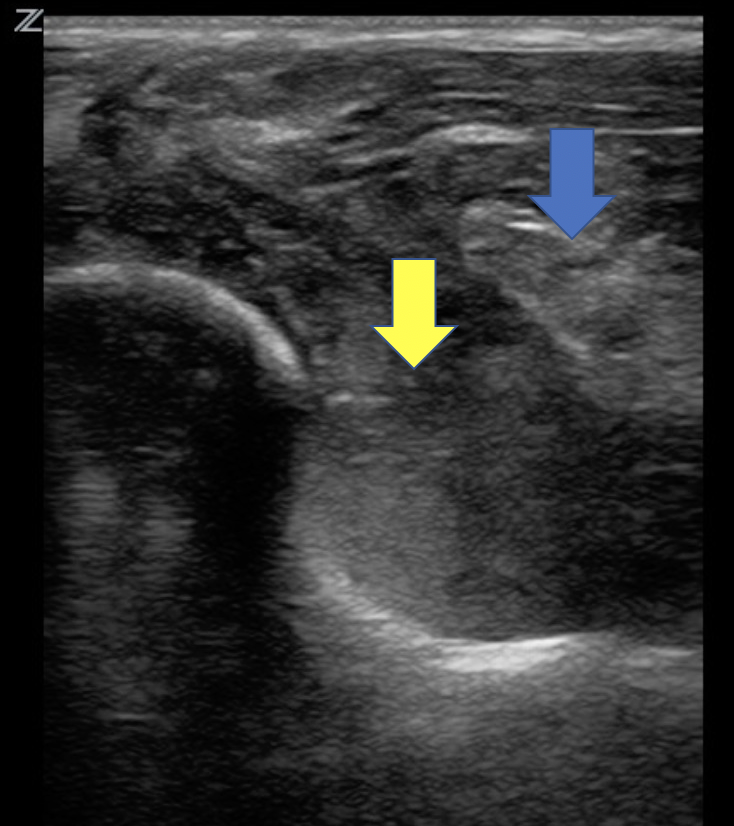

Fratura Supracondilar: Imagem 2, Corte transversal, Lipo-hemartrose

Cotovelo direito: ruptura da linha hiperecoica que representa o córtex supracondilar (seta vermelha). Líquido misto hipoecoico e hiperecóico superficial ao córtex representando hemolipoartrose (seta amarela). Protuberância do coxim adiposo posterior além da linha umeral (seta azul).